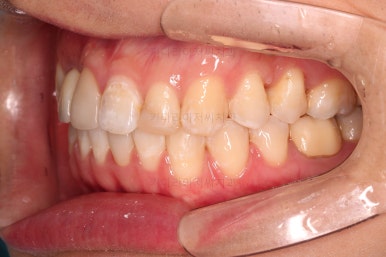

임플란트 완료시 모습인데요.

교합도 잘 맞고 임플란트도 잘 완성되었네요.

매복치아도 손상 없이 잘 배열이 되었고, 교합도 좋게 마무리 되었습니다.

크게 바꿀 필요가 없었던 얼굴모습은 거의 그대로 유지를 했고요. 웃을 때의 치열의 정렬된 느낌은 개선되었습니다.

매복치, 유치, 결손치 등 기능적인 부분들이 모두 잘 개선되었습니다.